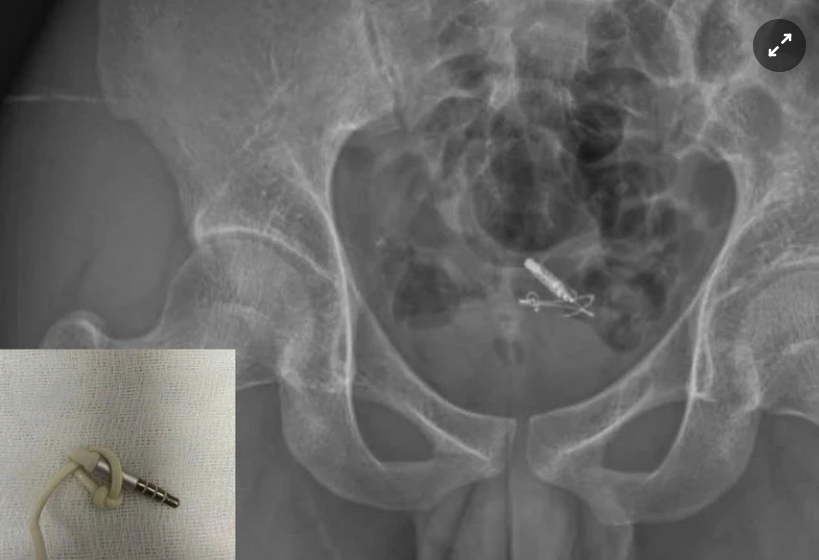

Đoạn tai nghe nằm trong bàng quang bệnh nhân trên phim X-quang. Ảnh: BVCC.

Tại đây, các bác sĩ xác định đây là trường hợp dị vật gây tổn thương niệu đạo. Kết quả chụp X-quang và siêu âm cho thấy dị vật nằm trọn trong bàng quang.

Ê-kíp tiến hành nội soi gắp dị vật thành công, lấy ra một đoạn dây cáp tai nghe kèm 1 jack cắm 3.5 mm dài khoảng 10 cm, bảo tồn nguyên vẹn cấu trúc bàng quang và niệu đạo.